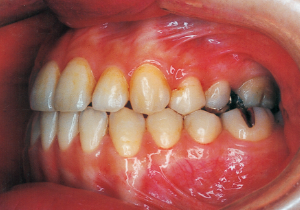

This case presented with Class III malocclusion and significant negative overjet from the early mixed dentition. Regular observation was conducted, and Phase I treatment was initiated after the eruption of the anterior teeth, improving the anterior occlusal relationship and molar relationship. Subsequently, regular observation continued toward the completion of the permanent dentition. However, due to vigorous mandibular growth, orthodontic treatment including surgery became necessary.

Aware that treatment would be challenging, we proceeded with the first phase of treatment based on the current functional status and anticipated developmental implications (7). During the mixed dentition phase, the body responds readily to treatment, allowing for relatively rapid tooth movement and changes in jaw position (8,9). Subsequently, once freed from mechanical stimulation, growth continues according to inherent predispositions, often appearing to disregard occlusal functional efficiency (10,11). These changes are clearly observable on cephalometric radiographs (12). After confirming the extent and direction of growth, we decided to incorporate surgical intervention into the treatment plan and wait until the age when growth begin to decline.

Reflecting on the course of treatment, one cannot help but marvel at the strength of the inherent biological program. At the same time, it makes one ponder how much artificial influence the body can allow and adapt to. While it would be difficult to say the long-term work in the first phase was suddenly meaningless, we must consider how much value it held for the overall treatment. The tongue is always positioned low due to its anatomical relationship within the facial structure. While it is understood that this low tongue position affects the dental arch, current treatment methods offer no solution. In such cases, we are acutely aware of the limited scope of what we can do.